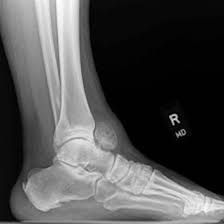

A NCCT (non-contrast computed tomography) of the left ankle joint is a radiology scan that uses X-rays and a computer to create images of the left ankle joint bones and its soft tissues to detect abnormalities in the left ankle joint. It is an effective technique to diagnose issues like injuries in the tendon, fracture to the bones, trauma to the left ankle and infections in the left ankle joint.